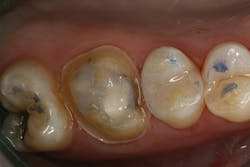

The clinical case in Figure 3 illustrates a patient who presented with a large, failing restoration containing cracks and decay. The patient was interested in an all-ceramic restoration. Occlusion was checked with articulating paper prior to treatment with a CAD/CAM restoration (figure 4). All previous restorative materials were removed from the tooth (figure 5). The tooth was restored using Grandio Core Dual Cure (Voco) build-up material (figure 6). A crown preparation was completed for a chairside CAD/CAM crown using the CEREC system (Dentsply-Sirona). The material of choice for this restoration was IPS e.max CAD (Ivoclar Vivadent), which is seen in Figure 7 after milling and in precrystallization form. The restoration was tried in and then polished, glazed, and placed in the oven for crystallization. The internal surface was then etched with 4.9% hydrofluoric acid, rinsed, and then coated with a silane coupler to create an optimal surface for bonding with the resin luting agent. The tooth was isolated and cleaned prior to etching. Once etched, the adhesive bonding agent (Futurabond U) was activated to mix the two liquids within the single-dose blister package. The blister seal was broken with the bonding agent brush and the adhesive was applied and agitated for 20 seconds. The adhesive was lightly dried for five seconds and then cured with an LED curing light for 10 seconds. A dual-cured adhesive resin luting agent (Bifix QM) was dispensed into the crown with its automix syringe (figure 8). The crown was seated and excess cement was removed after a two-second light cure. The tooth was then flossed and occlusion was checked (figure 9). The patient was very satisfied with the final result.

Figure 6: Teeth after restoration with Grandio Core Dual Cure build-up material (Voco)